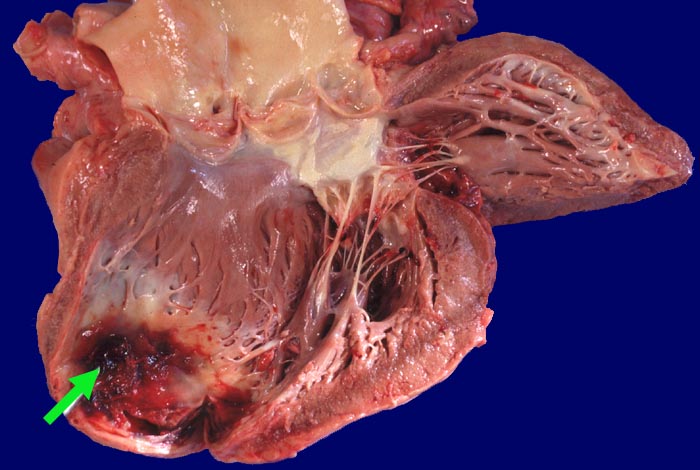

PathoPic ID 348 - Herzwandaneurysma mit Thrombose

Herzwandaneurysma mit Thrombose

vaskulär / Durchblutungsstörung

Herz links

Kardiovaskuläres System

Wandverdünndung und Ausbuchtung im Bereich einer Myokardinfarktnarbe der Herzspitze. Dem Aneurysma ist wenig

►

thrombotisches Material aufgelagert.

Cor bovinum (700g). Alter diskontinuierlicher Myokardinfarkt der rechten Herzkammer. Subakuter Myokardinfarkt der Hinterwand. Morbus embolicus.